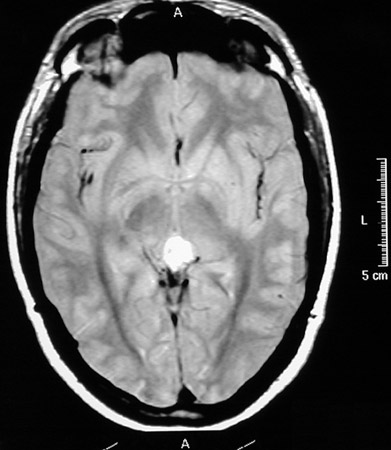

In the sagittal T1 weighted MRI scan above there is mass lesion in the region of the pineal gland. This is a pineocytoma. Below this mass appears bright in axial view post gadolinium injection.